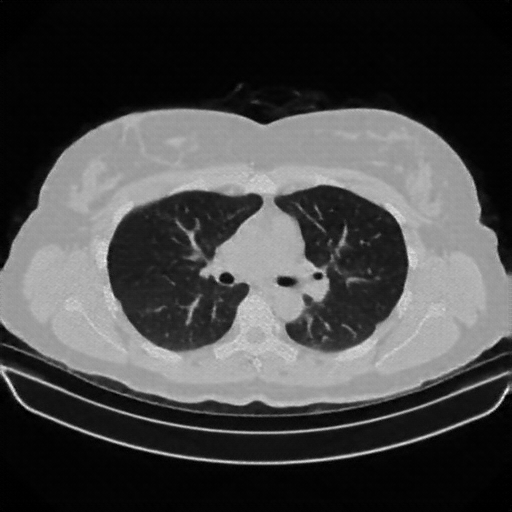

Original NATIVE CT scan (input)

Full window (WL 1023.5, WW 4095 β†’ Low βˆ’1024, High +3071)

Lung window (WL -600, WW 1500 β†’ Low βˆ’1350, High +150)

Mediastinum window (WL 40, WW 400 β†’ Low βˆ’160, High +240)